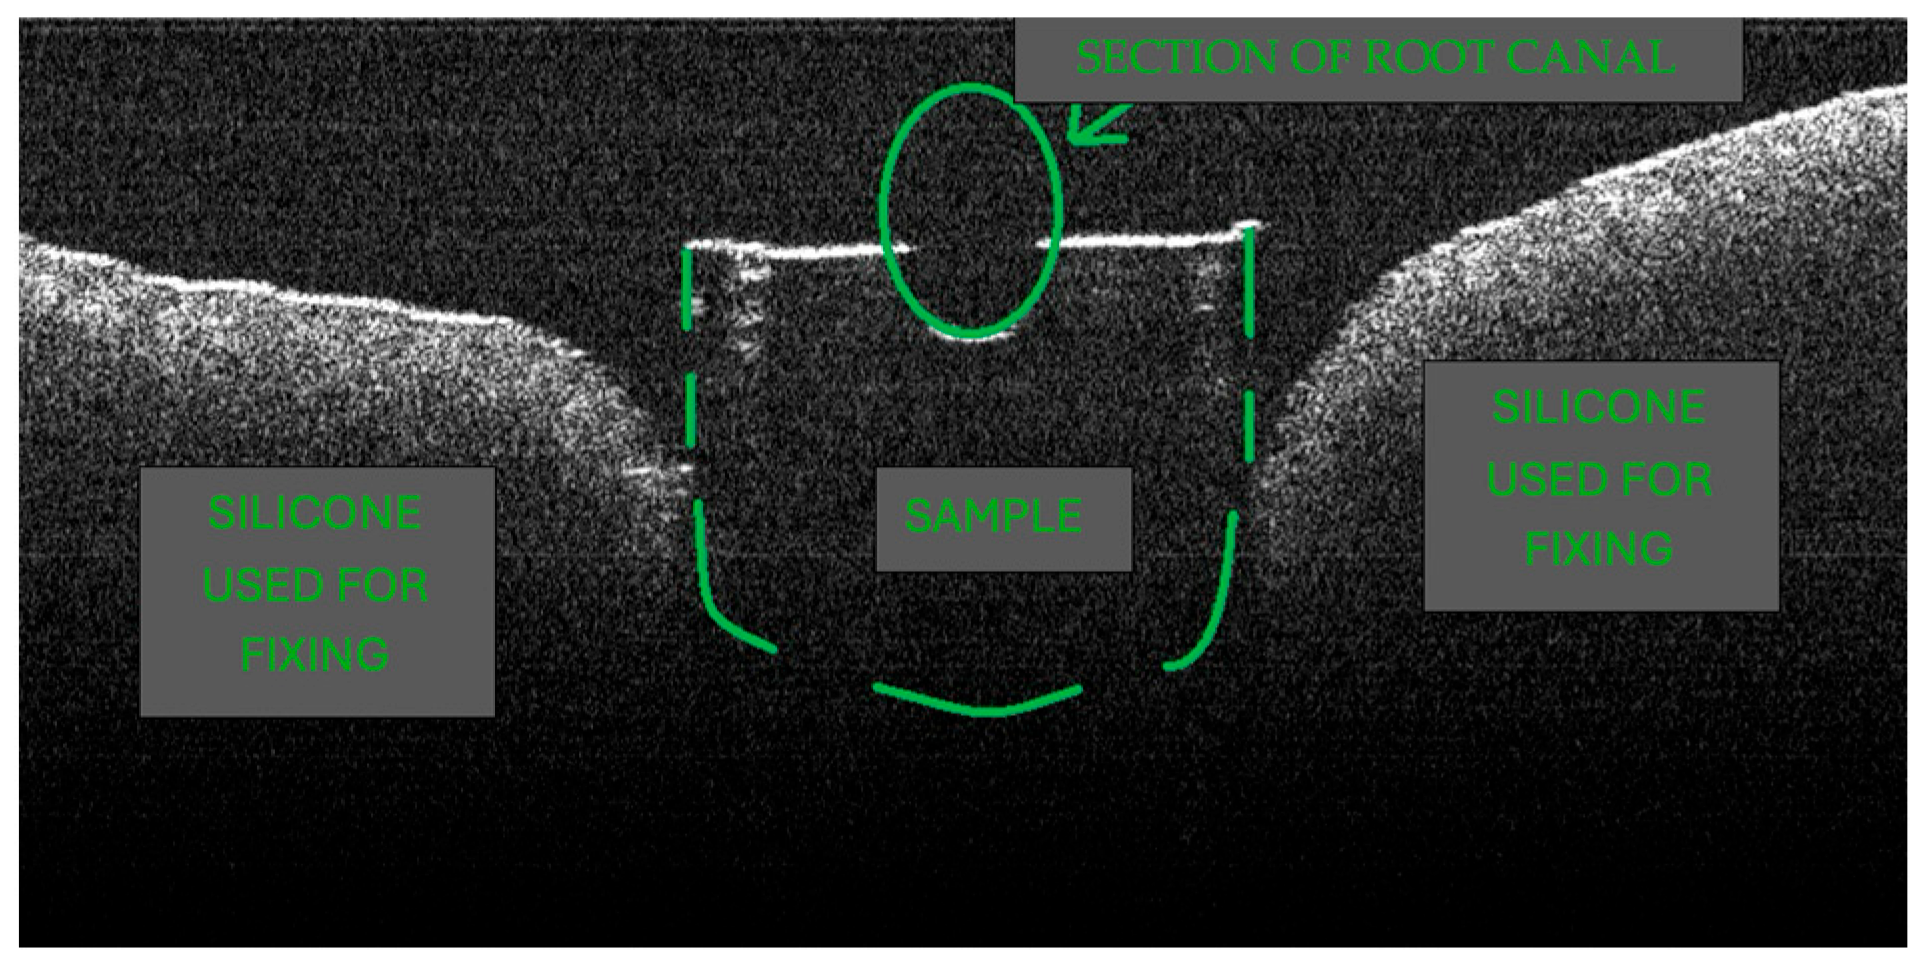

2.5. OCT Imaging Acquisition

3.2. Defining OCT Signatures: Alterations vs. Artefacts